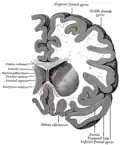

The caudate nuclei are near the center of the brain, sitting astride the thalamus. There is a caudate nucleus in each hemisphere of the brain. Each nucleus is C-shaped, with a wider "head" (caput in Latin) at the front, tapering to a "body" (corpus) and a "tail" (cauda). Sometimes a part of the caudate nucleus is called the "knee" (genu).[6] The caudate head receives its blood supply from the lenticulostriate artery; the tail of the caudate receives its blood supply from the anterior choroidal artery.[7]

The head and body of the caudate nucleus form part of the floor of the anterior horn of the lateral ventricle. The body travels briefly towards the back of the head; the tail then curves back toward the anterior, forming the roof of the inferior horn of the lateral ventricle. This means that a coronal section (on a plane parallel to the face) that cuts through the tail will also cross the body and head of the caudate nucleus.